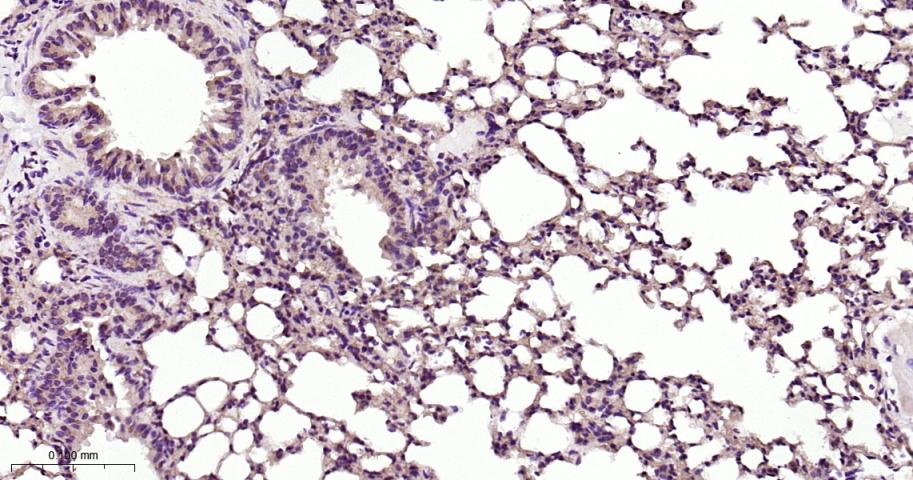

Paraformaldehyde-fixed, paraffin embedded Rat Lung; Antigen retrieval by boiling in sodium citrate buffer (pH6.0) for 15 min; Antibody incubation with PKC Monoclonal Antibody, Unconjugated(bsm-62952R) at 1:200 overnight at 4°C, followed by conjugation to the bs-0295G-HRP and DAB (C-0010) staining.

Paraformaldehyde-fixed, paraffin embedded Mouse Lung; Antigen retrieval by boiling in sodium citrate buffer (pH6.0) for 15 min; Antibody incubation with PKC Monoclonal Antibody, Unconjugated(bsm-62952R) at 1:200 overnight at 4°C, followed by conjugation to the bs-0295G-HRP and DAB (C-0010) staining.